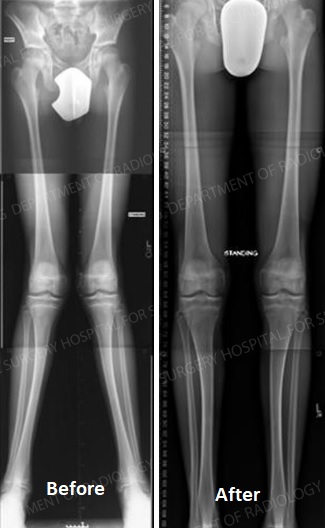

Medications, walking supports and altering activity levels may no longer be helpful after the knee disease progresses beyond a certain level. If you are at this stage, Total Knee Replacement (TKR) surgery is the best treatment option, as it corrects leg deformity, relieves pain and allows you to easily perform your daily activities.

In knee replacement we perform :

Hip replacements surgery can be performed traditionally or by using what is considered a minimally-invasive technique. The main difference between the two procedures is the size of the incision. During standard hip replacement surgery, you are given general anesthesia to relax your muscles and put you into temporary deep sleep. This will prevent you from feeling any pain during the surgery or have any awareness of the procedure. A Spinal Anesthetic may be given to help prevent pain as an alternative. The doctor will then make a cut along the side of the hip and move the muscles connected to the top of the thighbone to expose the hip joint. Next, the ball portion of the joint is removed by cutting the thighbone with a saw. Then an artificial joint is attached to the thighbone using either cement or a special material. After surgery a patient can : Play Golf, Climb Stairs, Drive a Car, Sit Crossed Legs.

Indications for Hip replacement are :